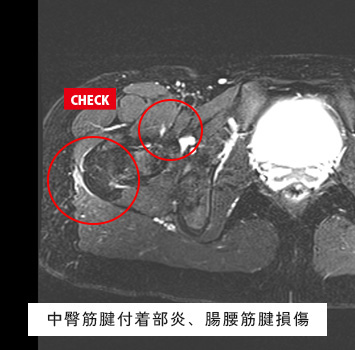

股関節MRIチェック

このような方におすすめします。

• 股関節が痛い

• 股関節が動かしづらい、クリック音がする

• スポーツや仕事で股関節を痛めた、痛みが治らない

筋肉と関節痛みのMRIチェック名古屋なら

レントゲン検査では分からない骨、筋肉、腱、関節唇などの様子が

がたった10分の検査で評価出来ます!

スポーツ選手、左股関節痛が続く、レントゲンで異常なし

転倒後の股関節痛、レントゲンで異常なし

料金:¥17,600(税込)

ご予約はこちら

股関節唇損傷、大腿骨頭壊死症、変形性股関節症、FAI(大腿骨寛骨臼インピンジメント)、関節リウマチなどの炎症性疾患、関節水腫、骨腫瘍、疲労骨折、滑液包炎、感染性股関節炎 など